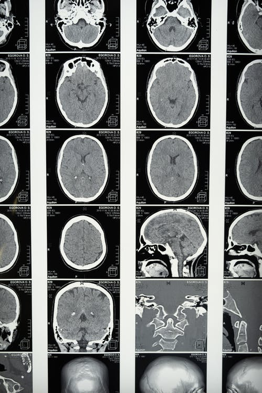

A CT scan uses X-rays to look inside the body and produce images. CT scans are very quick and used in emergencies, such as for suspected brain tumours, bleeding on the brain, or strokes.

MRI scans use magnetic fields for brain imaging. MRI scans produce more detailed images, and can be used for tumours, bleeding on the brain, issues with blood vessels in the brain, inflammation or investigating the spinal cord.

MRI scans take much longer than CT scans and are therefore not used in emergencies. They do, however, produce much higher quality images.

A brain scan may show white spots on the brain. These white spots form part of a migraine diagnosis as they are found in the brains of migraine patients. The spots are called White Matter Hyperintensities, which are brain lesions that can cause a very severe headache or migraine.